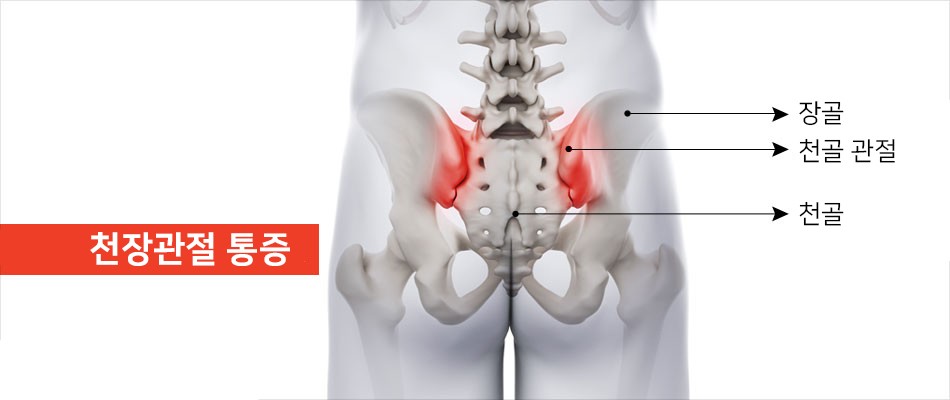

천장 관절 증후군

천장관절은 골반의 좌우측에 있는 골반뼈와 천골을 연결하는 관절입니다. 이 관절의 문제는 천골에 통증을 유발할 수 있습니다. 긴 척추를 골반까지 무너뜨려 안정성을 높여주는 관절입니다. 근육과 인대가 단단히 연결되어 있기 때문에 트러블이 잘 생기지 않습니다. 주변 인대가 손상되면 관절이 불안정해져 허리, 엉덩이, 허벅지 주변에 통증을 유발할 수 있다.